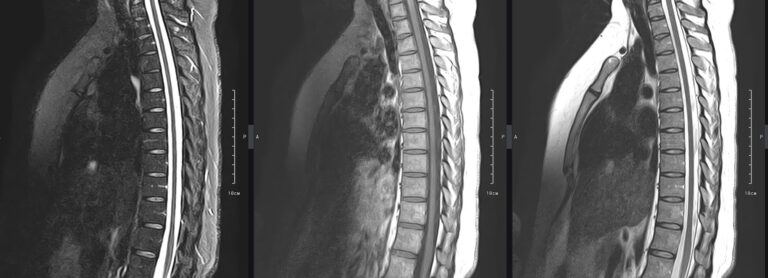

МРТ является современным высокоточным исследованием грудного отдела позвоночника, с помощью которого можно диагностировать различные заболевания, в том числе воспалительные, дегенеративные и опухолевые процессы. Преимуществом данного метода является его безопасность (отсутствие рентгеновского излучения), безболезненность, неинвазивность, при этом высокая информативность.

Клиника «Доступная медицина» оснащена новейшим томографом экспертного класса TOSHIBA VANTAGE TITAN 1,5 Тесла, который позволяет получать превосходные изображения с мельчайшей детализацией всех структур исследуемой области. Это позволяет ставить точный диагноз и выявлять различные заболевания позвоночника на самой ранней стадии.

С помощью МРТ грудного отдела выявляют следующие заболевания позвоночника:

• новообразования;

• степень повреждения спинного мозга в случае переломов тел позвонков;

• грыжи Шморля;

• травматические повреждения тел позвонков и остистых отростков (трещины, переломы, смещения и пр.) — при недоступности КТ;

• разрывы, растяжения связок;

• травмы спинного мозга, нервных корешков;

• протрузии;

• грыжи межпозвонковых дисков;

• остеохондроз позвоночника;

• стеноз спинномозгового канала;

• сосудистые патологии;

• остеомиелит, спондилодисцит;

• рассеянный склероз;

• спондилоартроз;

• спондилез.